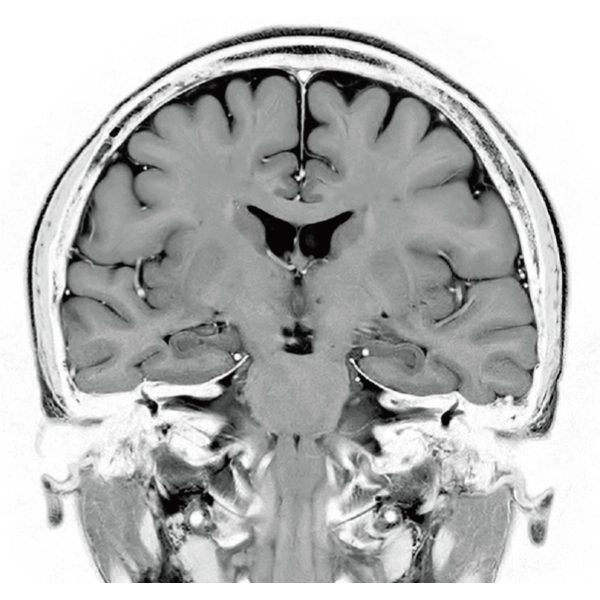

"DLR" is applicable to all body parts and promotes high speed imaging and diagnostic efficiency

IP-RAPID x DLR Plus can also shorten imaging time, allowing more images to be taken in the same examination time.

Additional imaging, such as different image types and cross sections, can be added to the conventional examination to increase the amount of information and make the diagnosis more reliable.